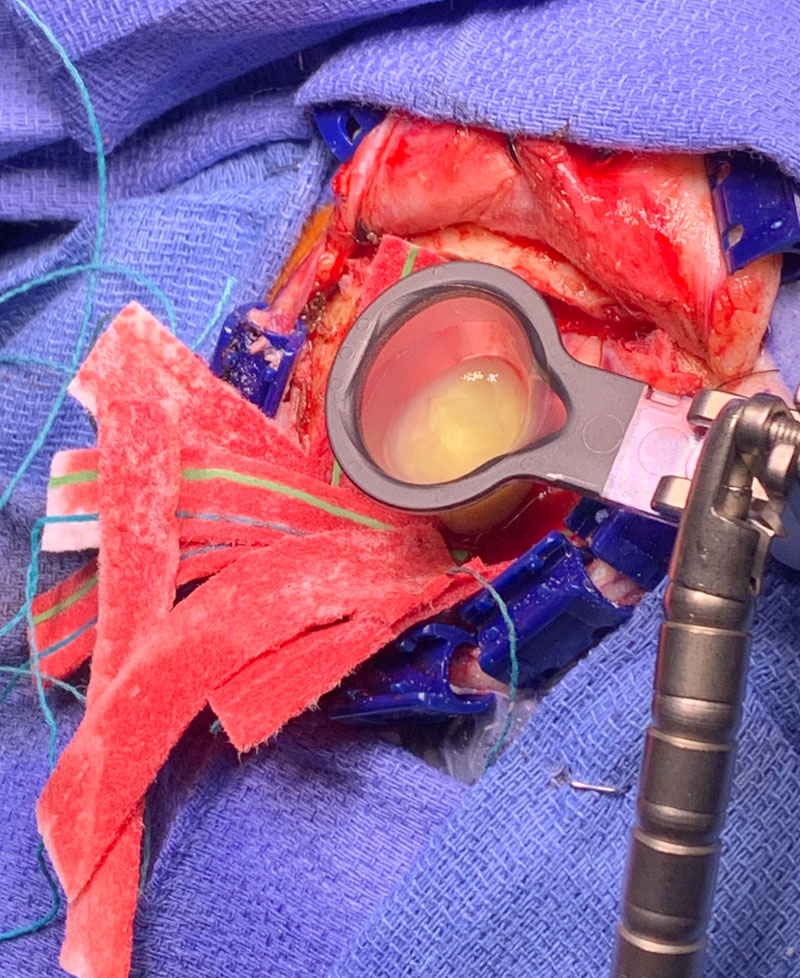

Postoperatively, the patient was started on broad spectrum IV antibiotics, under the supervision of an Infectious Disease consult. Clinically, the patient gradually recovered. Within weeks, the patient had fully recovered and was neurologically intact. Gram stains were suspicious for the presence of bacteria (encapsulated cocci). Cultures never grew out any organisms. The patient was treated with several weeks of broad spectrum IV antibiotics. The patient made a full recovery. (Image 3, axial post contrast MRI from 3 months post-op shows resolution of brain abscess and surrounding edema. )

Image 3: Axial post contrast MRI from 3 months post-op shows resolution of brain abscess and surrounding edema.